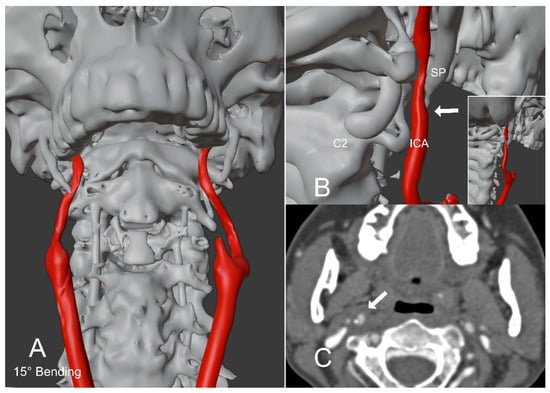

Figure 2.

Patient with Eagle Syndrome in a flexed position of the head. (A,B) show a 3D reconstruction model of a patient with Eagle Syndrome in a flexed position of the head (15°). The model was created from the rest position CTA of the head and neck, applying a virtual bending of 15°. The right styloid process impinges the ipsilateral internal carotid artery tightening its caliber (arrow in (B). The enclosed image in (B) represents a postero-lateral perspective with a zoomed-out view. (C) shows the CTA image of the subject in a flexed position of the head (15°). The right styloid process impinges the ipsilateral internal carotid artery (arrow). SP = Styloid process; ICA = Internal carotid artery; C2 = C2 Vertebral body.